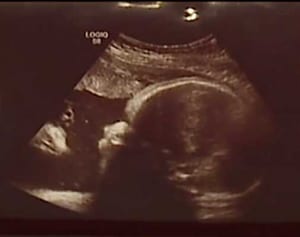

胎児エコー写真に写っていた驚きのモノとは?

2017/08/24 19:00米ペンシルベニア州に住むザック・スミスさんとその婚約者アリシア・ジークさんは第三子の出産を目前に控え、病院で子宮内エコーを撮った。そこには、赤ちゃんと彼女を見つめるイエス・キリストが写っていたそうだ。「明らかに、娘を見ている顔が写っていました。気づいた瞬間泣きそうになりましたね。信じられません」とスミスさんは地元テレビ局FOX43に語る。スミスさんとジークさんの間にはすでに2人の子どもがいるが、長 -